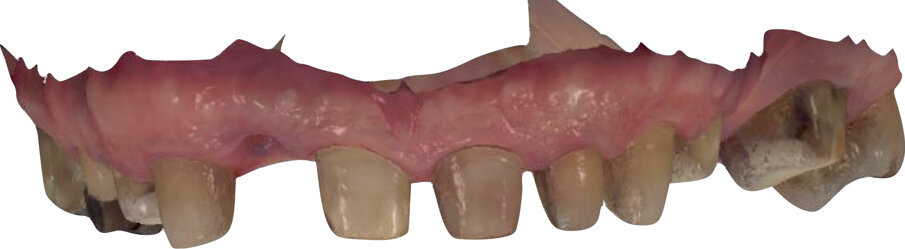

Un paziente di 66 anni, con anamnesi patologica di NIDDM ben compensato e cardio-vasculopatia ischemica in buon compenso farmacologico, si presenta alla nostra attenzione per ascesso parodontale alla radice residua del dente 1.2 e per multiple fratture dei manufatti protesici esistenti (Figg. 1-6). È evidente la presenza di grave malocclusione con perdita di VDO, usure e fratture dei restauri protesici e dei denti residui, presenza di abfractions cervicali. Il paziente evidenzia alla visita modesta dolenzia muscolare alla palpazione, specie a carico dei muscoli pterigoidei mediali e temporali, apertura della bocca ridotta e lieve rumorosità delle TMJ.

L’infezione a carico della radice del dente 1.2 è immediatamente attribuibile a frattura verticale con sondaggio positivo di 9 mm (Fig. 7). Estratta la radice di 1.2 fratturata, il paziente richiede una riabilitazione protesica fissa all’arcata superiore che preveda il minor numero possibile di interventi endodontici e chirurgici. Viene da noi proposta una riabilitazione protesica full arch che consenta, previo studio del caso gnatologico e terapia interlocutoria con provvisori in PMMA, la definizione di un’occlusione a funzione sequenziale in TRP per l’aumento controllato della VDO e la stabilizzazione dei rapporti articolari, ora visibilmente compromessi.